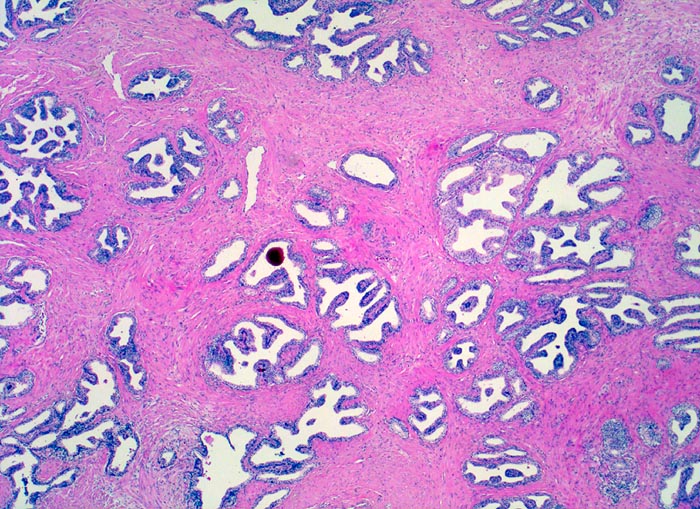

• Knotiges Parenchym.

• Organoid angeordnete, teils dilatierte grosse Drüsen eingebettet in ebenfalls vermehrtes fibroleiomyomatöses Stroma.

• Drüsen ausgekleidet von hochprismatischen sekretorischen Zellen (innen) mit unscheinbaren Nukleolen und durchgehender flacher Basalzellschicht (aussen).

• Konzentrisch geschichtetes hypereosinophiles Sekret in einigen Drüsenlumina (Corpora amylacea).

• Herdförmig geringes chronisches Entzündungsinfiltrat.